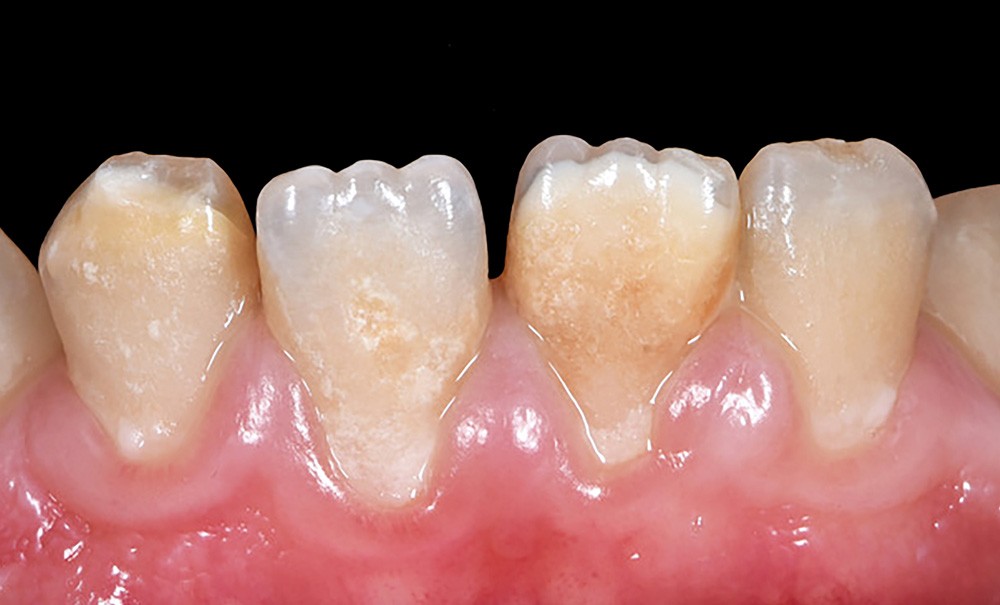

Hypominéralisation Dent De Lait. MolarIncisorHypomineralisation (MIH) Universitätsklinikum Giessen und Marburg L'hypominéralisation des molaires et des incisives, qu'est-ce que c'est ? Cette maladie qui affecte l'émail des dents de l'enfant peut avoir des conséquences importantes sur sa santé bucco-dentaire à moyen et à long terme Les incisives permanentes peuvent aussi être atteintes.

L'hypominéralisation des molaires et des incisives, qu'est-ce que c'est ? Cette maladie qui affecte l'émail des dents de l'enfant peut avoir des conséquences importantes sur sa santé bucco-dentaire à moyen et à long terme Elle touche au moins une ou les quatre premières molaires permanentes

L'hypominéralisation des molaires et des incisives, souvent abrégée en MIH (Molar Incisor Hypomineralization), est une affection dentaire touchant particulièrement les enfants L'hypominéralisation des incisives et molaires, connue sous l'acronyme MIH, est une condition qui compromet la qualité de l'émail dentaire et peut avoir des conséquences importantes sur la santé bucco-dentaire Apprenez ce qu'est la MIH, cette maladie des dents de l'enfant et pourquoi une prise en charge rapide peut éviter des complications.